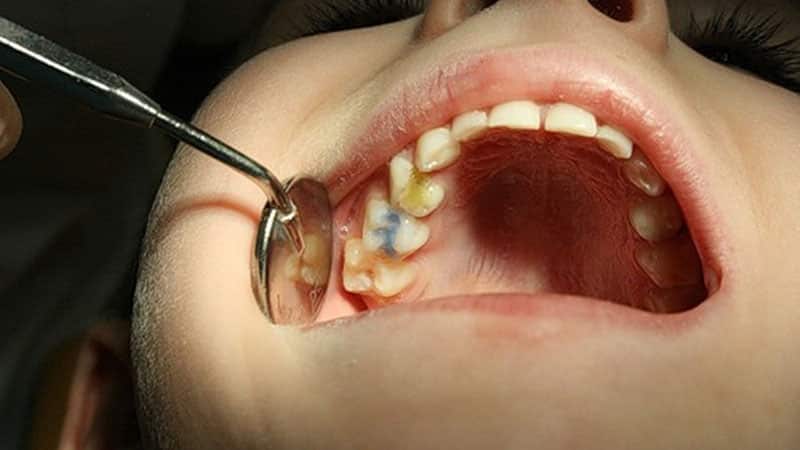

Традиционные способы лечения острого детского пульпита

Из-за риска возникновения осложнений и серьезных состояний, которые может вызвать пульпит у детей с молочными зубами, лечение в первую очередь сосредоточено на устранении этих угроз. Конечно, проще всего удалить поврежденный зуб, но такая процедура может негативно сказаться на психическом состоянии ребенка и повлиять на формирование прикуса.

В государственных стоматологических учреждениях и даже в некоторых частных клиниках чаще всего применяется метод девитальной ампутации. Этот способ давно известен, многократно проверен и считается достаточно щадящим для ребенка, так как не затрагивает корневую систему зуба. Процесс выглядит следующим образом:

- Сначала на обнаженный участок нерва (да, в молочных зубах действительно есть нервы) накладывается специальная паста с мышьяком на 1-2 дня или девитализирующий состав без мышьяка на неделю.

- При следующем визите в корневые каналы помещают специальные пасты, которые обладают противомикробным действием на пульпу и «мумифицируют» ее, предотвращая дальнейшее развитие гнойного процесса.

- Завершающий этап включает пломбирование зуба.